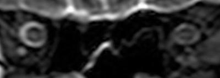

Intracranial pressure (ICP) needs to be directly measured before and after long duration flights to determine if microgravity causes the increased ICP. On the ground, lumbar puncture is the standard method of measuring cerebral spinal fluid pressure and ICP,[4][38] but this carries additional risk in-flight.[2] NASA is determining how to correlate ground-based MRI with inflight ultrasound[2] and other methods of measuring ICP in space is currently being investigated.[38]

To date, NASA has measured intraocular pressure (IOP), visual acuity, cycloplegic refraction, Optical Coherence Tomography (OCT) and A-scan axial length changes in the eye before and after spaceflight.[39]